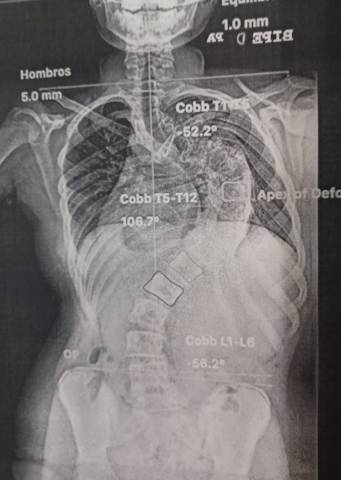

El Hospital Nuestra Señora del Rosario ha sido escenario de un nuevo hito médico, al acoger con éxito la primera intervención en la sanidad privada madrileña de corrección quirúrgica de escoliosis con tecnología 7D. Este novedoso navegador, que permite al cirujano, gracias a una recreación virtual de la columna del paciente, ser más preciso en la colocación de los tornillos correctores, reduciendo considerablemente los riesgos, ha sido incorporado por el equipo del Dr. Rafael González Díaz, jefe de la Unidad de Cirugía de Columna del centro.

Este revolucionario Sistema Guiado por Imágenes de Visión Artificial, de 7D Surgical, solo se había empleado en Madrid en una operación similar, a cargo también del Dr. González Díaz y su equipo, en el Hospital Universitario Infantil Niño Jesús, en el que ejerce como jefe de servicio de la Unidad de Cirugía de Columna.

Previamente a la operación, se realiza una TAC al paciente, prueba que sirve al sistema quirúrgico 7D para recrear virtualmente un mapa topográfico de su anatomía. A partir de ahí y de que el cirujano señale tres puntos de referencia, el dispositivo señalará la orientación exacta para la introducción de los tornillos pediculares. Este registro se ejecuta en unos pocos segundos por lo que se puede repetir sin interrumpir el flujo de trabajo quirúrgico. Además, el sistema se puede recalibrar rápidamente si se golpea la matriz de referencia o si la anatomía del paciente ha tenido movilidad, una característica que ningún otro sistema de navegación puede ofrecer en la actualidad.